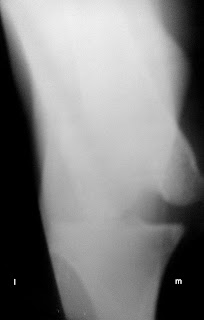

Se presenta en consulta Noa una galga de 23 Kg de peso con luxación lateral de rótula, rotura del ligamento colateral medial y rotura del ligamento cruzado anterior, la rodilla presenta aducción en su apoyo y esta completamente deformada tras un atropello.